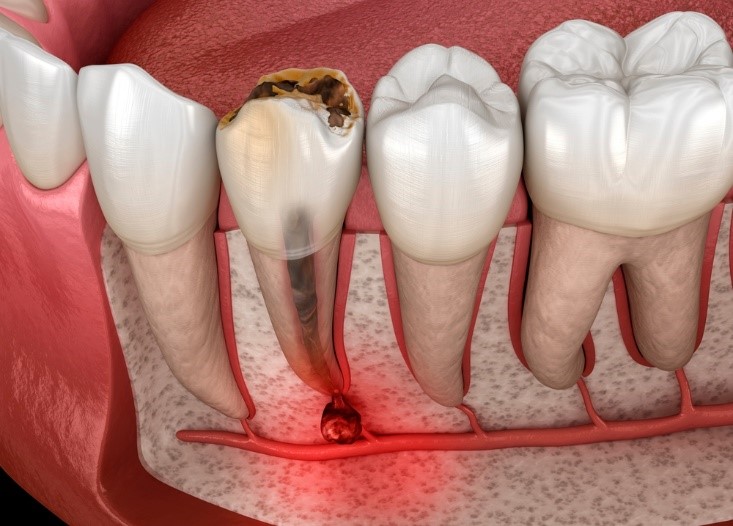

Viêm tủy răng có mủ là tình trạng tủy răng bị viêm nhiễm nghiêm trọng dẫn đến hình thành ổ mủ bên trong ống tủy hoặc quanh chân răng. Đây là giai đoạn nặng của bệnh lý và có thể dẫn đến nguy cơ mất răng cao nếu không phát hiện và điều trị kịp thời.

Khi vi khuẩn xâm nhập sâu vào tủy mà không được xử lý các ống tủy sẽ dần bị hoại tử. Ổ mủ khi hình thành sẽ lan rộng theo ống tủy đến chóp răng. Từ đó tấn công vào xương hàm gây đau nhức, sưng mặt thậm chí phải mổ để nạo mủ.

Khi tủy răng chết cấu trúc răng cũng bị ảnh hưởng nghiêm trọng. Chân răng sẽ bị lung lay, viêm quanh chóp lan rộng làm cho chiếc răng không còn giữ được.